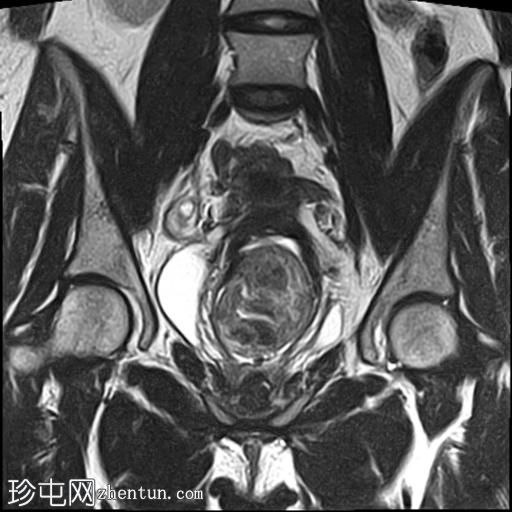

冠状位

T2加权像

子宫增大,前倾后屈,可见多发大小不一、位置各异的壁内肌瘤(主要位于Figo 2、5和6区)。

一个边界清晰的带蒂宫腔内肿块经扩张的宫颈管脱出。T1加权像上呈等信号,T2加权像上呈中低信号,周围环绕着高信号的子宫内膜,静脉注射对比剂后呈明显不均匀强化。

双侧卵巢外观正常,可见小卵泡。

MRI 影像特征最符合带蒂子宫肌瘤经扩张的宫颈管脱垂,并伴有多个子宫肌瘤。